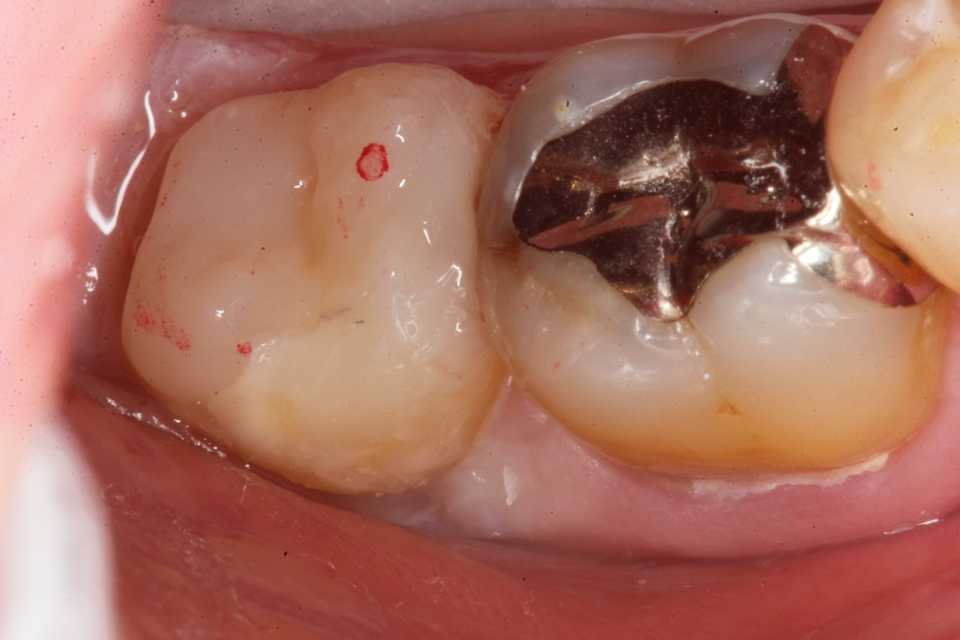

ストリップスを使わない隣接面CR(ダイレ… 2025.11.26

ストリップスを使わない隣接面CR(ダイレ… 2025.11.07